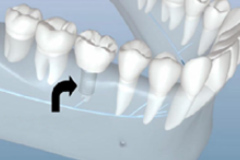

早期矫正

儿童优选 · 专为3~12岁儿童设计

量身定制 · 针对孩子不同情况定制矫正计划

正牙助萌 · 同步完成获得理想面型